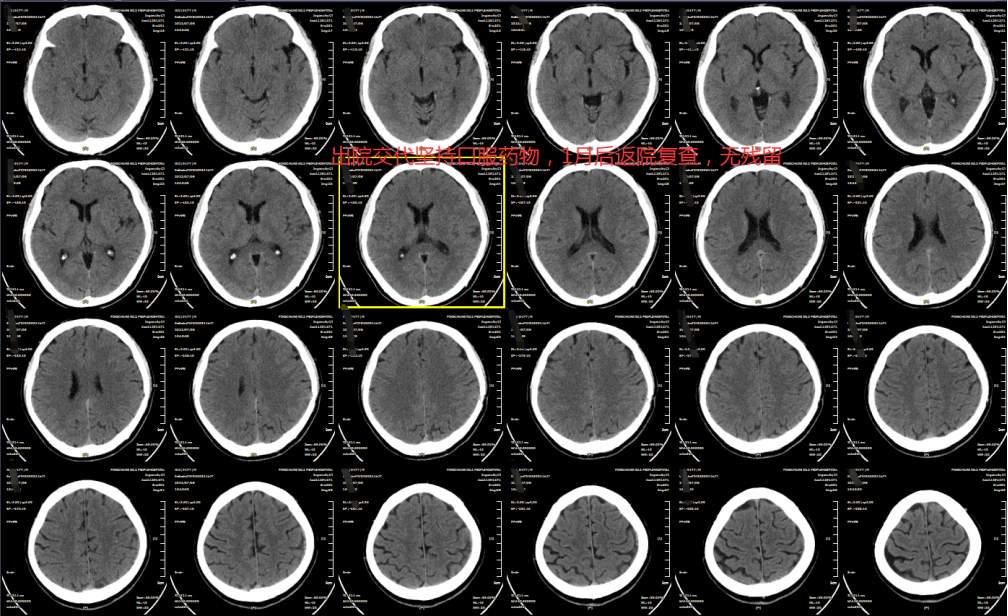

慢性硬膜下血肿,穷尽引流

患者 男,年龄 47岁,因“间断头晕10+天”入院。

查体:神清语利,右侧肢体灵活性稍差,余无明显异常。

入院CT提示左侧额颞顶部慢性硬膜下血肿,密度均匀。

术后复查

出院前。

1月后复查。